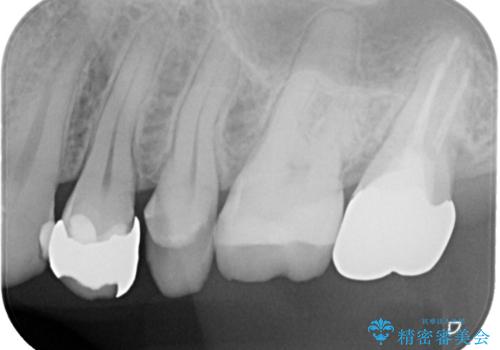

- 金属の詰め物が外れた状態で長期間過ごされた患者様が、歯を治したいとのことで来院されました。良好な長期予後が期待でき、歯質をできるだけ残せるセラミック治療を即日で行いました。

治療途中で虫歯も綺麗に除去しています。術後経過良好で、患者様も満足されています。他にも治療が必要な虫歯がありますので、順を追って治療する予定です。

今回の治療では、MarkⅡというセラミックのブロックを削り出して使用しています。従来からある、手で築盛して製作するタイプの修復物には気泡が発生しやすいのですが、これは歯に力がかかった際に破断点となりインレーが割れてしまう一因となります。MarkⅡブロックには気泡がありませんので、割れてしまうリスクを減らすことができます。